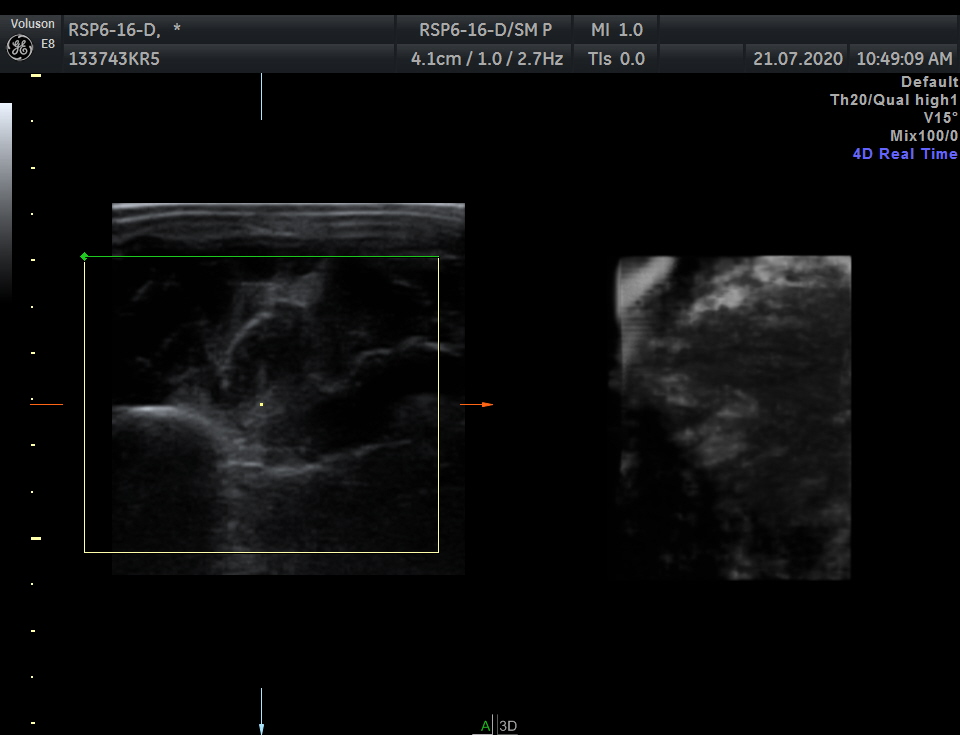

GE RSP6-16-D 3D/4D Linear

Breast, Small parts, Vascular and Musculoskeletal

18 – 6 MHz

VOLUSON, LOGIQ

Frequency Range: 18 – 6 MHz

GE RSP6-16-D 3D/4D Linear for Breast, Small parts, Vascular and Musculoskeletal

Compatible with GE Systems

VOLUSON E6

VOLUSON E8

VOLUSON E10

LOGIQ E9

LOGIQ S8